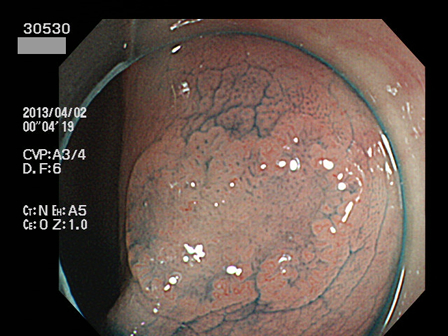

上記100名より抽出した平坦・陥凹型腺腫(=癌化の危険が高いが見落としやすい病変)の内視鏡写真

30500 30502 30504 30506 30510 30512 30513 30519 30520 30521 30523 30524 30526 30529 30530 30532 30533 30534 30535 30540 30543 30545 30546 30548 30551 30552 30554 30555 30558 30560 30561 30562 30564 30565 30568 30571 30572 30573 30574 30575 30576 30583 30584 30585 30586 30587 30588 30591 30592 30593 30596 30597・・・・・・の52名